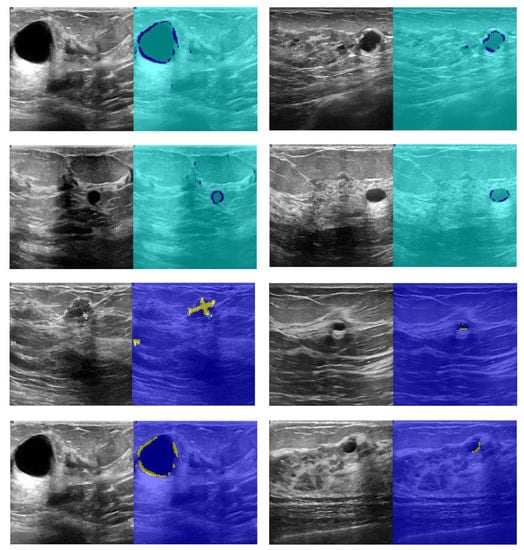

The segmentation results are shown in Figure 10. According to Figure 10, the first and third columns of the input image show the image infected with the cancerous tumor. Moreover, the other side of the image shows the segmentation results. Seventy percent of the images used for network training and 30% for test results start the process. The results of detecting the infected area are shown in the second and fourth columns of Figure 10. The resulting images should look like ground truth images. According to the results, the presented findings are almost similar to the model output. They have correctly identified the location of the tumor. To better increase the output, minor points in the results should be connected with morphological operations. Because the output points of the model were able to identify the approximate location and size of the tumor, we relate the tumor morphology to the original size of cancer. Figure 11 shows the approximate location and size of the tumor after morphological surgery. The results show that the proposed architecture can correctly identify the contaminated area.

Figure 10.

Results of CNN network cancer tumor segmentation.